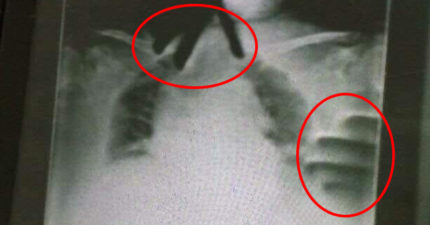

阿嬤住院突喘不過氣 X光驚現「無骨雙手掐脖」!主治醫出面證實了